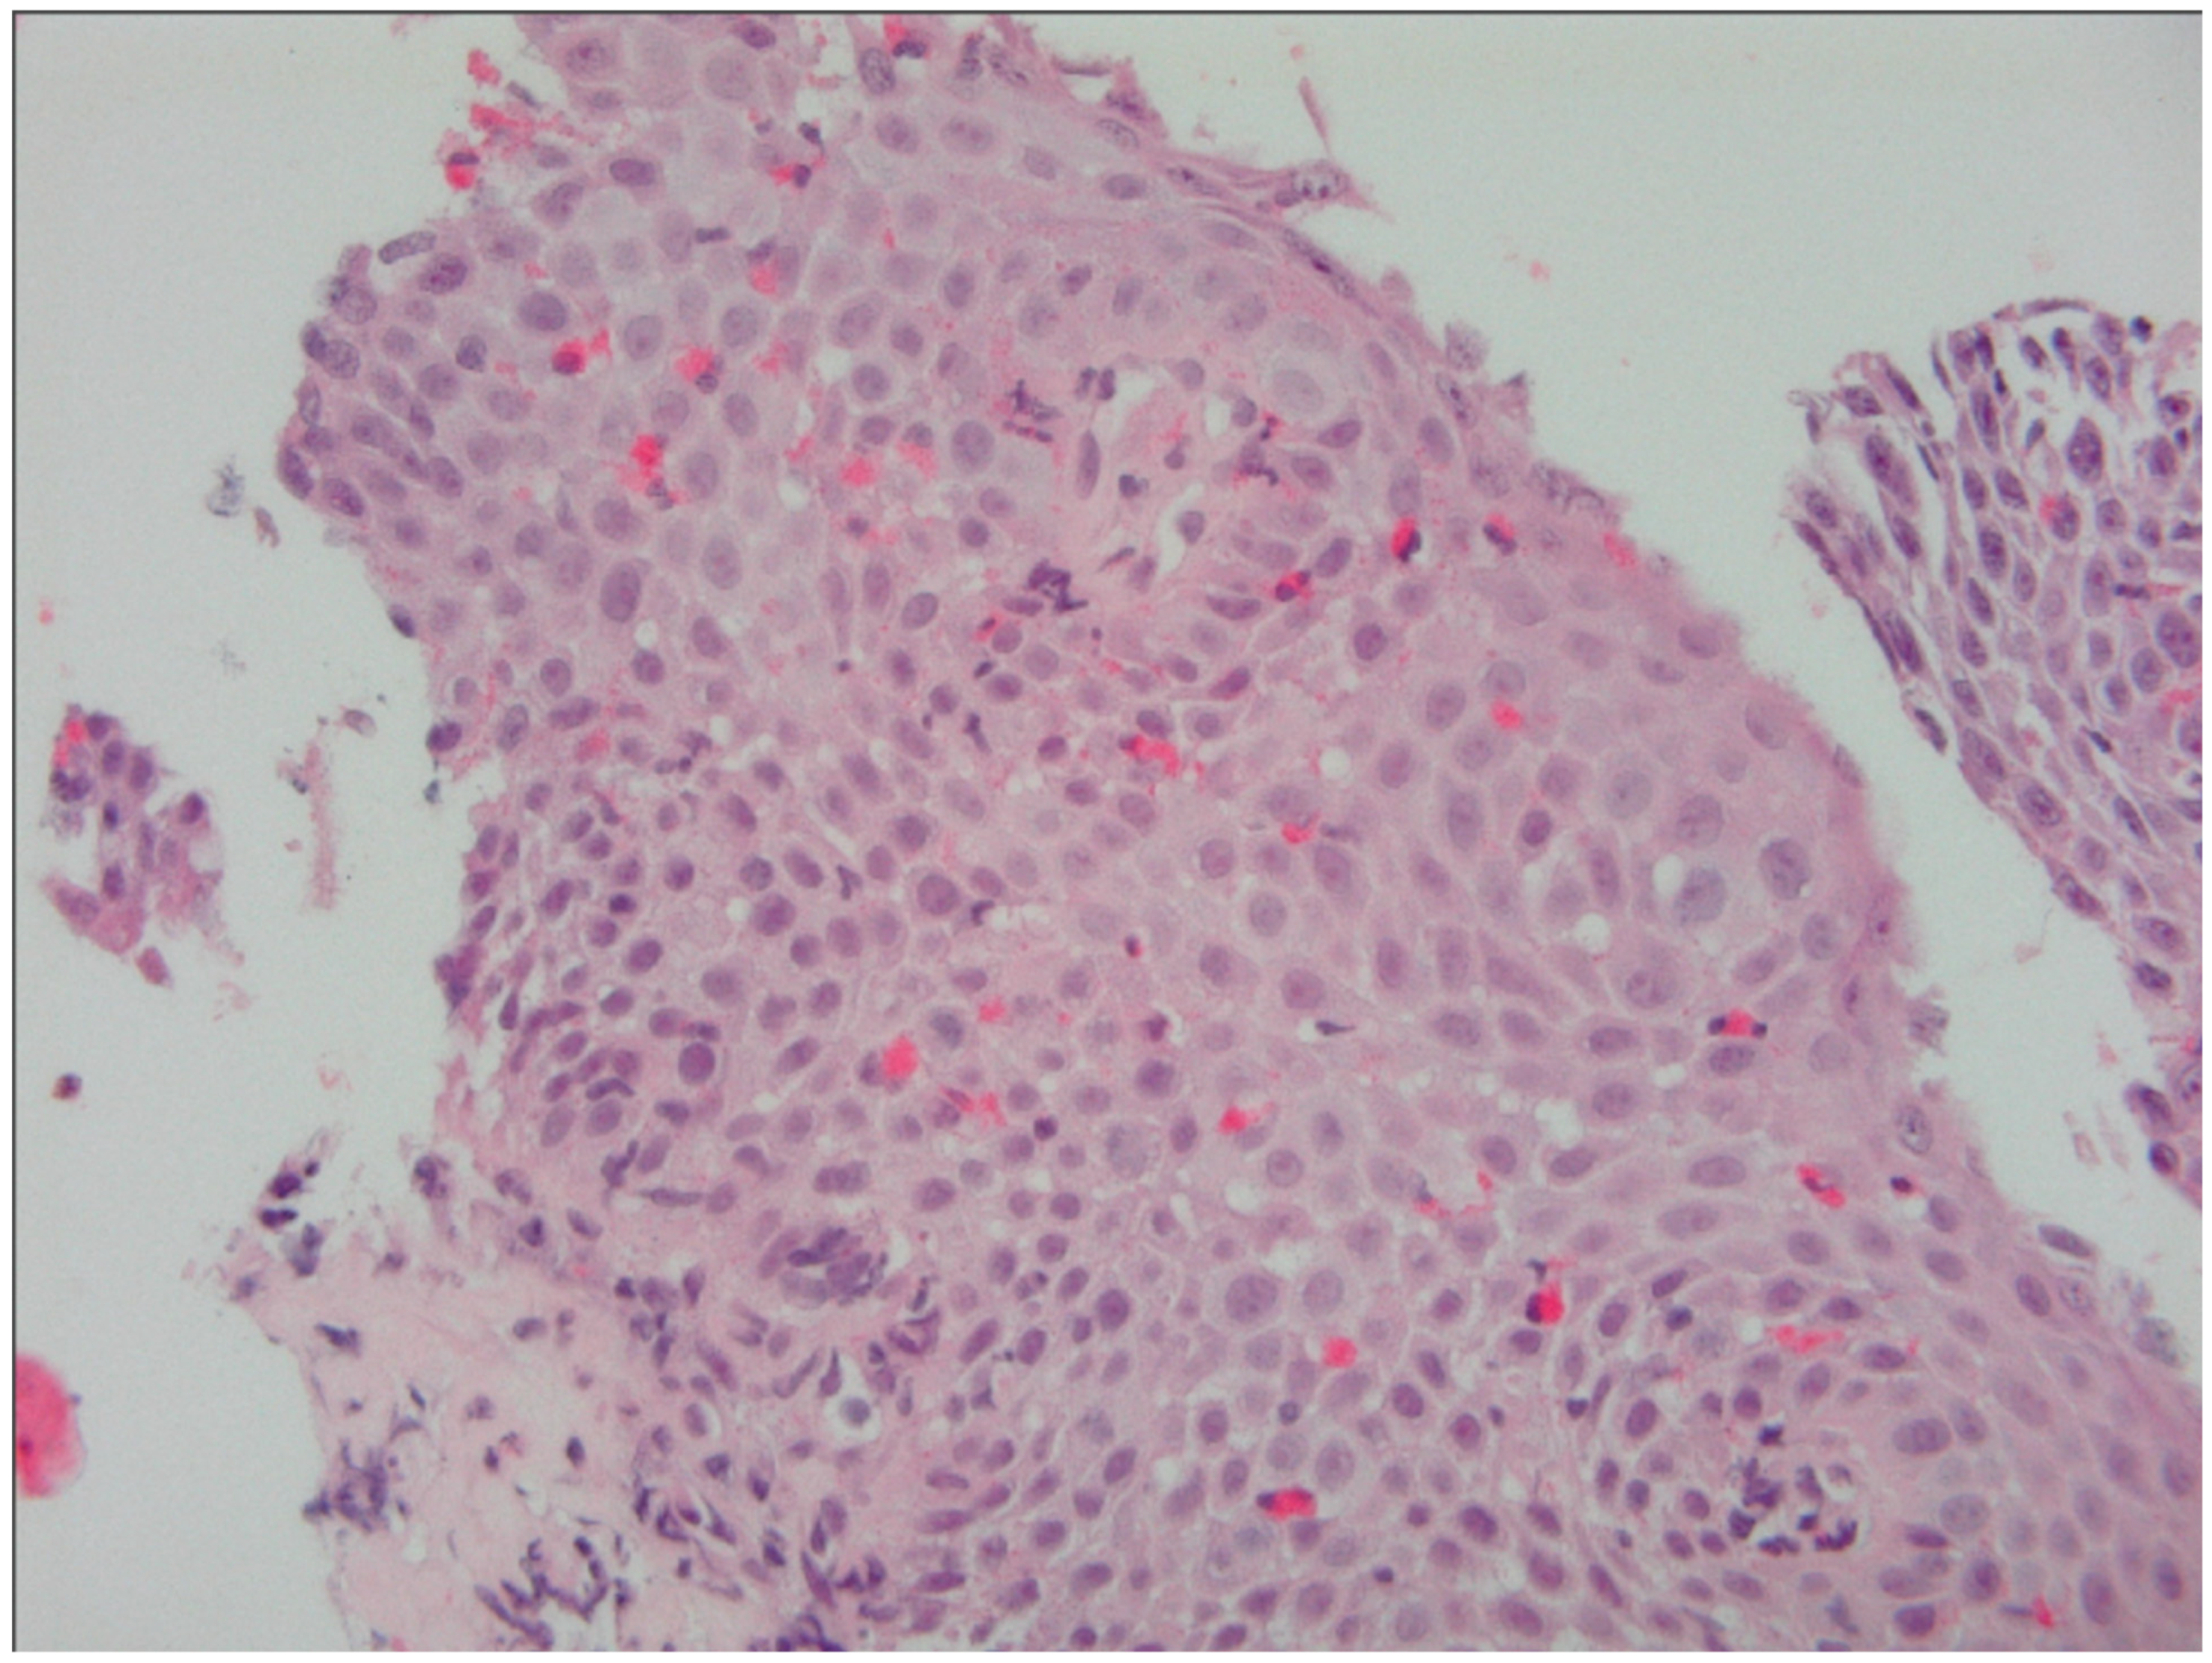

5.3. Histological Evaluation